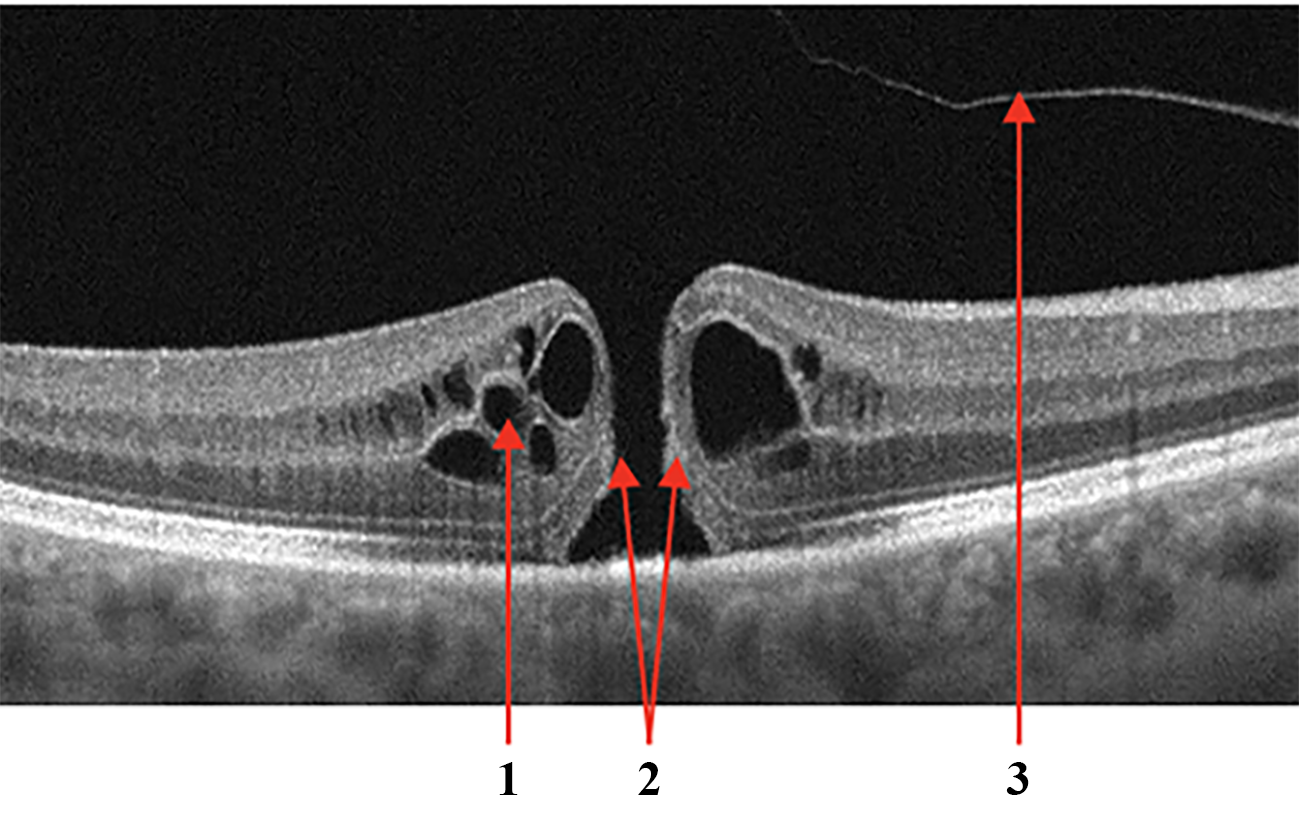

Fig.3 shows examples of AMD: the retinal profile is deformed, and the normal foveal architecture is disrupted. In Fig.3a the inner retinal layers are thinned and contain outer retinal tubulations or cystic spaces, highlighted with number 1. Subfoveolarly, a hyporeflective region is visible beneath the retinal pigment epithelium - in Fig.3a highlighted with number 2. Hyperreflective coloration of the choriocapilaris below the RPE layer atrophy is apparent. Local and diffuse decreases in the thickness of the choriocapillaris layer. Fig.3b shows different fluid-filled spaces in the macular that may accompany the clinical features of AMD:

• Subretinal fluid - space between the RPE and the neurosensory retina, in Fig.2b is shown with number 1.

• Intraretinal fluid, a kind of hyperreflective cyst - a cyst in the inner retina, but the content differs in reflectivity - with a granular appearance indicating the presence of more reflective elements that may be cellular debris or protein that has leaked into the space, in Fig.2b is shown with number 2.

• Sub-retinal pigment epithelial fluid - a hyporeflective space between Bruch’s membrane and the basolateral membrane of the RPE in Fig.2b is shown with number 3. This may be due to the breakdown of fluid regulation by the ion channels of the RPE [31].

Figure 3: Age-related Macular Degeneration (AMD). Markers (a): 1 - outer retinal tubulation or cystic spaces; 2 - Subretinal fibrosis causing distortion of the macular and hyporeflectivity of the underlying choroid. Types of fluid (b): 1 - subretinal fluid; 2 - intraretinal fluid; 3 - sub-retinal pigment epithelial fluid accumulation.